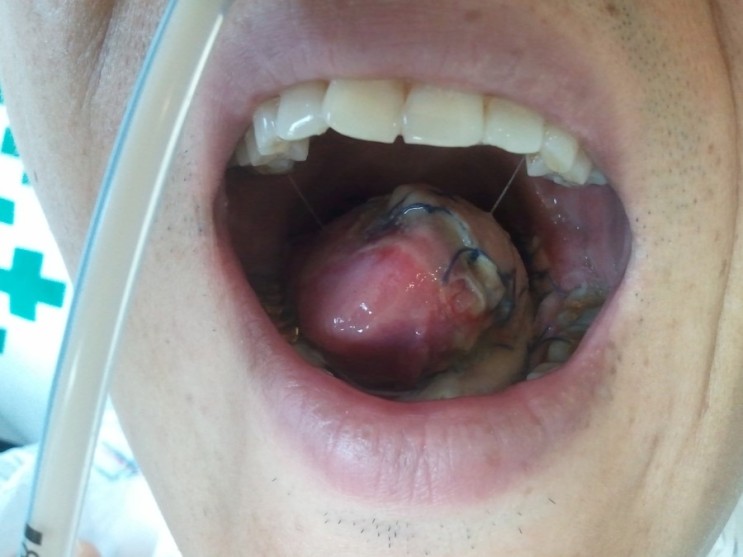

설암은 혀에서 발생하는 대표적인 구강암으로 혀 질병의 종류로는 혀암, 혀균열, 혀 성장 장애, 혀 작열감 증후군 등이 있다. 혀에 생기는 병은 대부분 생명에 지장을 주지 않는다. 그러나, 혀암은 치료율이 낮으며 설근부에 암이 생기면 조기 발견을 해도 5년 생존률은 60~70%에 불과하다. 다른 암에 비해 다른 조직으로의 전이가 매우 빠르며, 설암은 구강의 암 중에서도 가장 많으며 구강의 점막에 어떤 이상이 생기면 아주 빠른 시기에 통증이나 이상한 감을 민감하게 느끼는 것이 보통이다.

- 입 안에 생긴 종괴 혹은 부종(붓기)이 3주 이상 지속되는 경우

입 안에서 평소에 없던 것이 만져지는 경우, 단순한 염증이거나 또는 염증 때문에 생긴 단순한 물혹일 수 있다. 그러나 본인이 생각하기에 뭔가 이상해 보이는데 원래부터 있던 것인지 아니면 새로 생긴 것인지 헛갈릴 때는 일단 좌우를 비교해야한다. 대칭적으로 보인다면 대개 정상일 가능성이 많으며, 비대칭이거나 의심스러운 점이 있으면 가까운 의원에서 진찰을 받는 것도 좋다. 또한 붓기가 생겨 3주가 지나도 없어지지 않는다면 전문의의 진료를 받을 것을 권장한다.

설암을 방치하면 전이 가능성이 높아 조기 발견되어 빠른 치료가 중요하다. 설암을 치료하기 위해서는 수술을 통하여 절제하는 것이 중요하며, 초기에 경계 확보를 신중하게 하고 암을 절제하여 봉합하는 과정을 통하여 치료가 이루어지게 된다. 이 과정으로 인하여 혀의 반이상을 절제한 경우에는 팔이나 다리 등에서 살을 이식하여 혀를 재건하는 수술을 진행하게 될 수도 있다. 만약, 치료를 위해 혀의 극히 일부를 잘랐거나 재건을 한 경우에는 발음의 차이는 있겠지만 음식을 섭취한다거나 일상생활을 하는데는 전혀 무리가 없다.